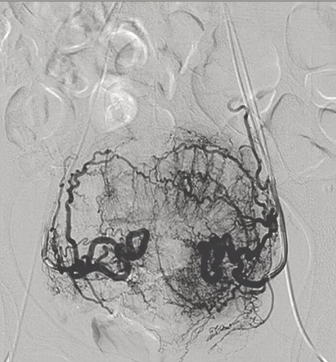

42岁,月经过多伴贫血(Hb 8 g/dL),痛经,腹部膨隆逐渐增加;以前2次怀孕;1堕胎;1活产;未有进一步怀孕计划

PVA 350-500 + 500-700 um

弥漫性子宫腺肌症,病变梗死

子宫容积减少